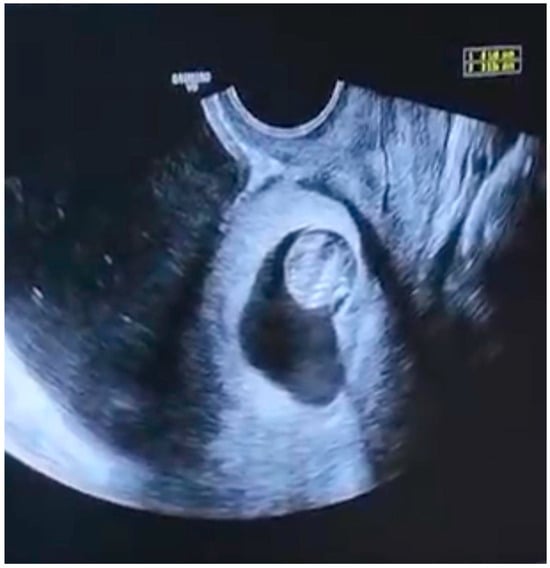

This Special Issue of Diagnostics, an open access journal, on the topic of “Advances in Diagnostic and Operative Hysteroscopy, 2nd Edition” will publish a broad range of original papers covering the full spectrum of the hysteroscopic technique. Hysteroscopy is a valuable tool in modern minimally invasive gynecologic surgery; as such, the journal invites high-quality submissions on current research and review articles, aiming to shed light on controversies and clinical practice. In addition to research and reviews, it also welcomes meta-analyses, practice guidelines, and more.

Topics of interest include general gynecology, infertility, pediatric and adolescent gynecology, Mullerian anomalies, gynecologic oncology, pelvic medicine, pros and cons of various hysteroscopic techniques, etc. This Special Issue focuses on the diagnosis, prediction, prevention, and treatment of various gynecological disorders.